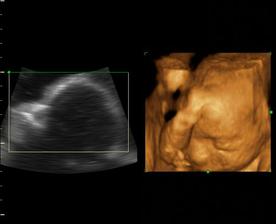

a z Emy Silvie je nkoniec Natalka...teraz uz 4 a pol roka, netrpezlivo cakajuca na braceka, ktory restie v brusku...🙂